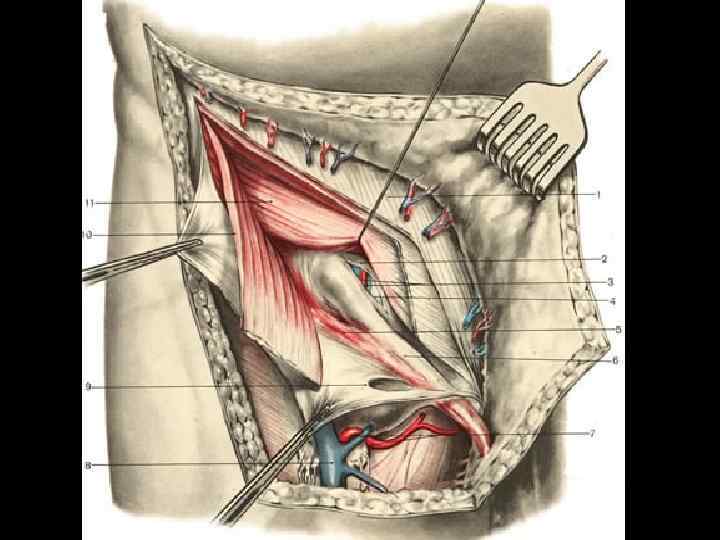

ПАХОВАЯ ГРЫЖА У мужчин – 96 % всех грыж

Косая паховая грыжа

ПРЯМАЯ И КОСАЯ ПАХОВЫЕ ГРЫЖИ

ВРОЖДЕННАЯ И ПРИОБРЕТЕННАЯ ПАХОВЫЕ ГРЫЖИ